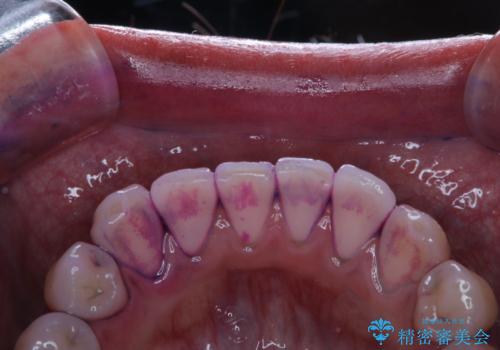

歯垢染色液を使うと、一見きれいな歯でも染まっている所が全て歯垢(プラーク)なのがはっきり分かります。歯に付着した歯垢(プラーク)は肉眼では認識しにくいものです。完璧に磨けているつもりでも、磨き残しが残っているかもしれません。